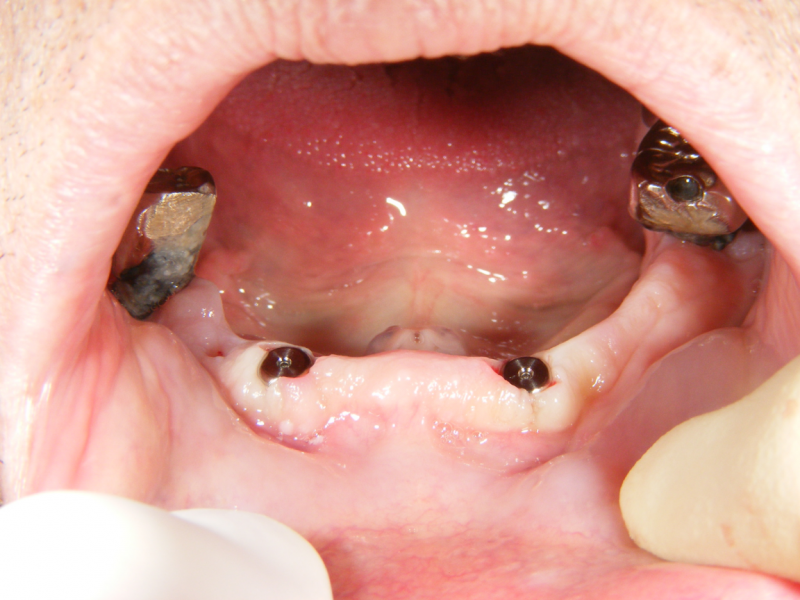

この状態で2か月待ちます。その間も、義歯は使用できます。

インプラントと骨が結合した後、ロケーターと言われるアタッチメント(ボタンのようなもの)をインプラントと義歯に装着します。

このシステムで、義歯を固定することができます。義歯が安定することで食事内容が大きく改善されます。

義歯の青い部分は、ゴム製なので経年劣化して義歯の維持力が落ちます。

ゴムは数年に1度、定期的に交換する必要があります。